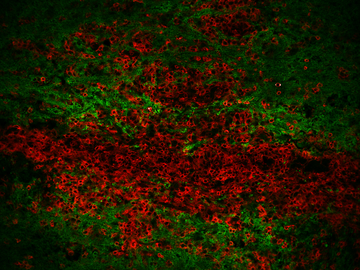

Striking Laboratory Data Images

Laboratory Data Gallery